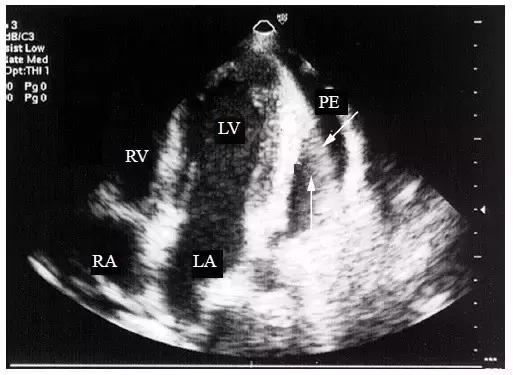

3.将探头置于心尖部,可见暗区中出现带状强回声,即“荡击波”征(图4),若液体以渗出为主,则在液体暗区内出现有规律摆动的带状回声,形如水草或飘带(图5)。

图4 大量心包积液时的“荡击波征”

将探头置于心尖部,大量心包积液暗区中出现带状强回声,即“荡击波”征(箭头所指)